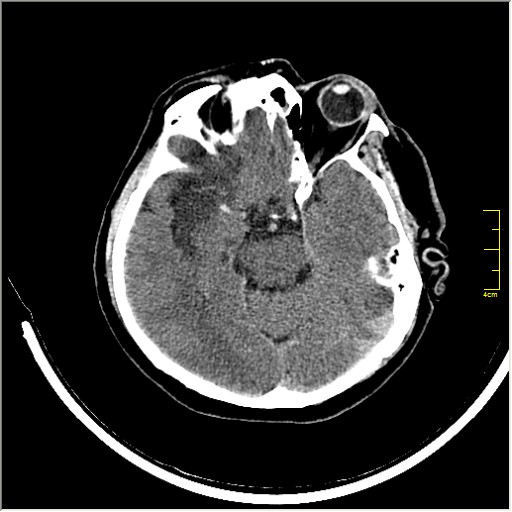

Пациентка Д. 64 года. Поступила с диагнозом ОНМК ???, жалобы на онемение и слабость в левой половине тела.

Ответ: Обратите внимание на правую среднемозговую артерию (MCA); М1 сегмент гиперденсен; сравните с другой стороной.

Этот признак называется [Dense MCA sign]; за счёт наличия тромбоза в её просвете. Этот признак является одним из ранних указующих КТ признаков при ишемическом инфаркте головного мозга. Более подробно об этом вы можете прочитать здесь: http://www.radiologyassistant.nl/en/483910a4b6f14.